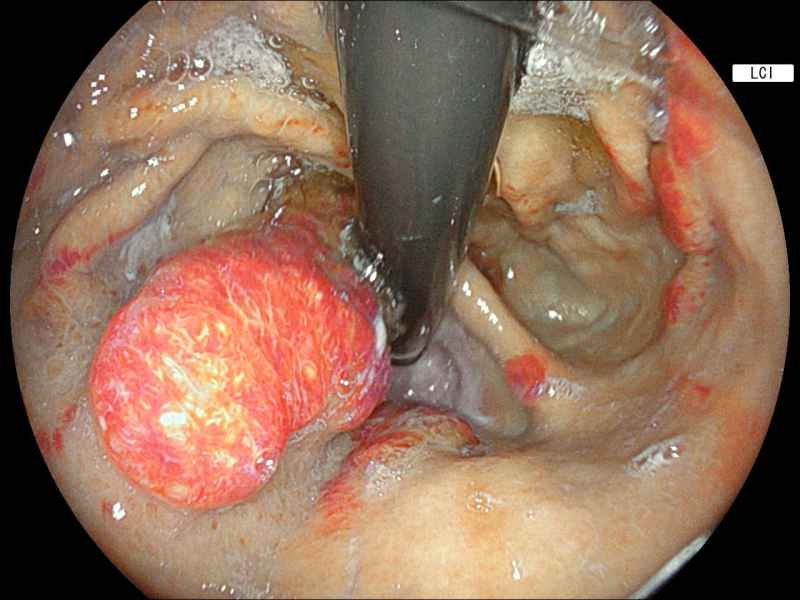

Hybrid endoscopic full-thickness resection of an appendicular laterally spreading tumour

Fotografia